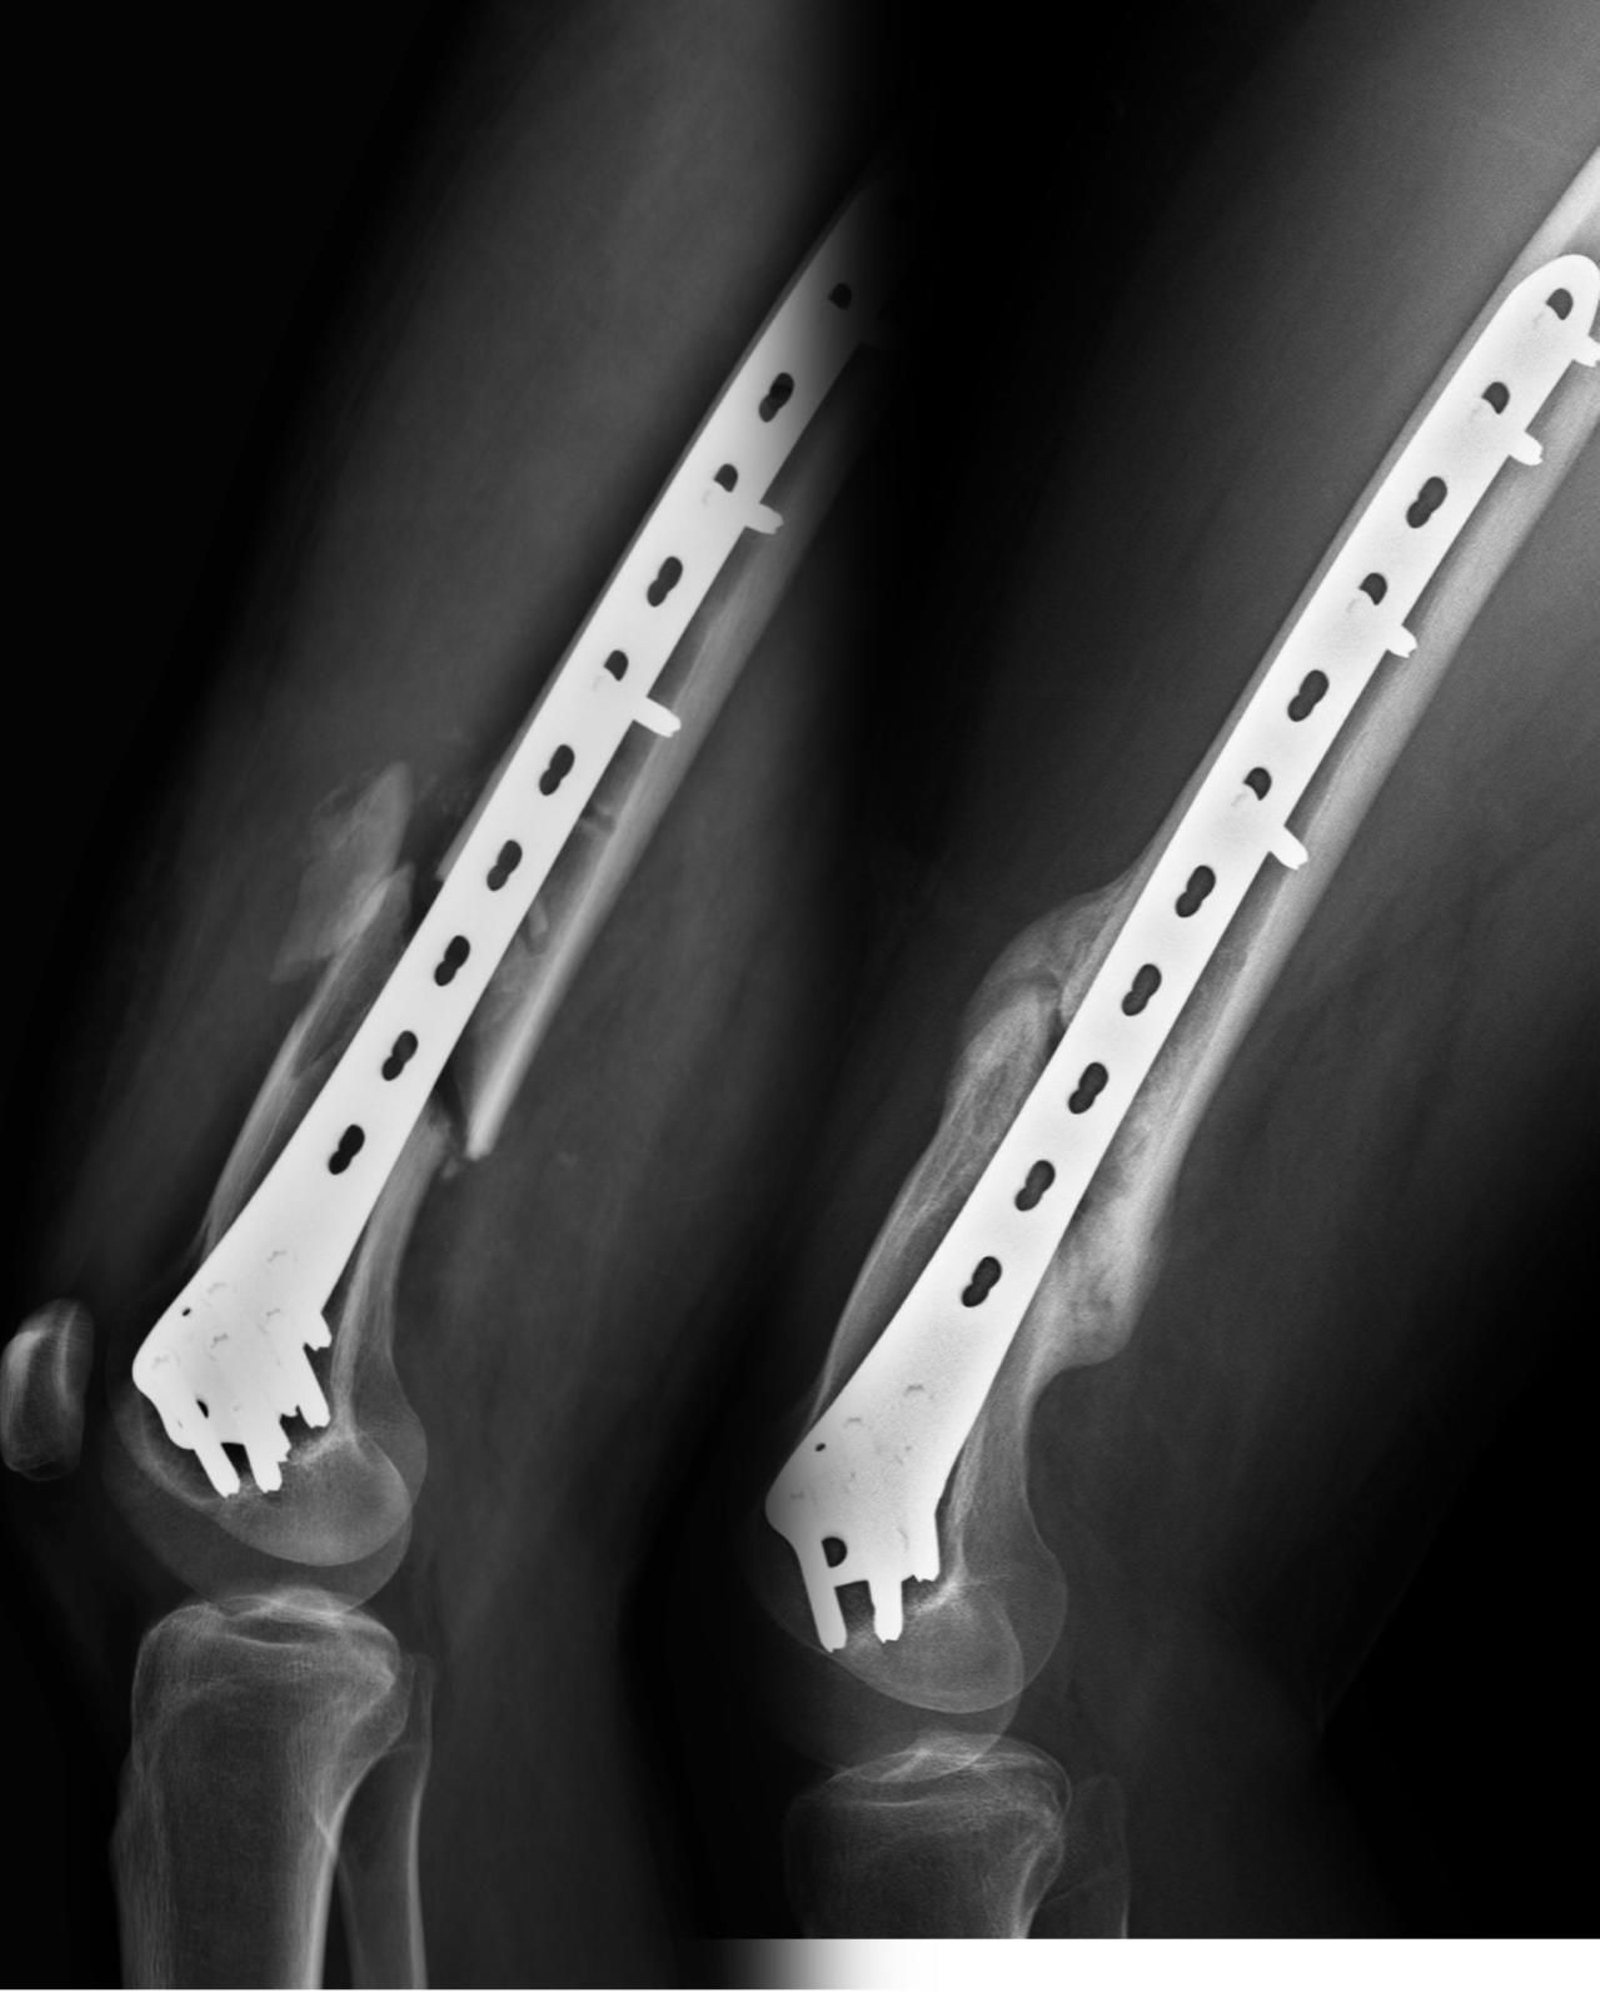

Radigrafía de una fractura en la que se ha empleado un tratamiento con ondas de choque.

Paciente de 21 años que sufrió en abril de 2023 un accidente de moto lo que le provocó una fractura abierta de fémur (el hueso quedó expuesto tras romper la piel). Fue operado y se le colocó una placa con tornillos. La reducción de la fractura no fue perfecta, quedando huecos entre los fragmentos, lo que hacía presagiar complicaciones para que consolidara. Acude a mi consulta en mayo y comenzamos a inyectar el plasma del propio paciente en el foco de fractura; además se le suplementó con una hormona para facilitar el aporte de calcio, vitamina D y sesiones de cámara hiperbárica.

También fue tratado con cuatro sesiones de ondas de choque. El resultado está siendo espectacular. De no consolidar la fractura (foto de la izquierda), al callo de fractura que se aprecia en la imagen de la derecha. La biología en algunas ocasiones necesita que le facilitemos el trabajo, y con los medios y la tecnología actual, es posible.